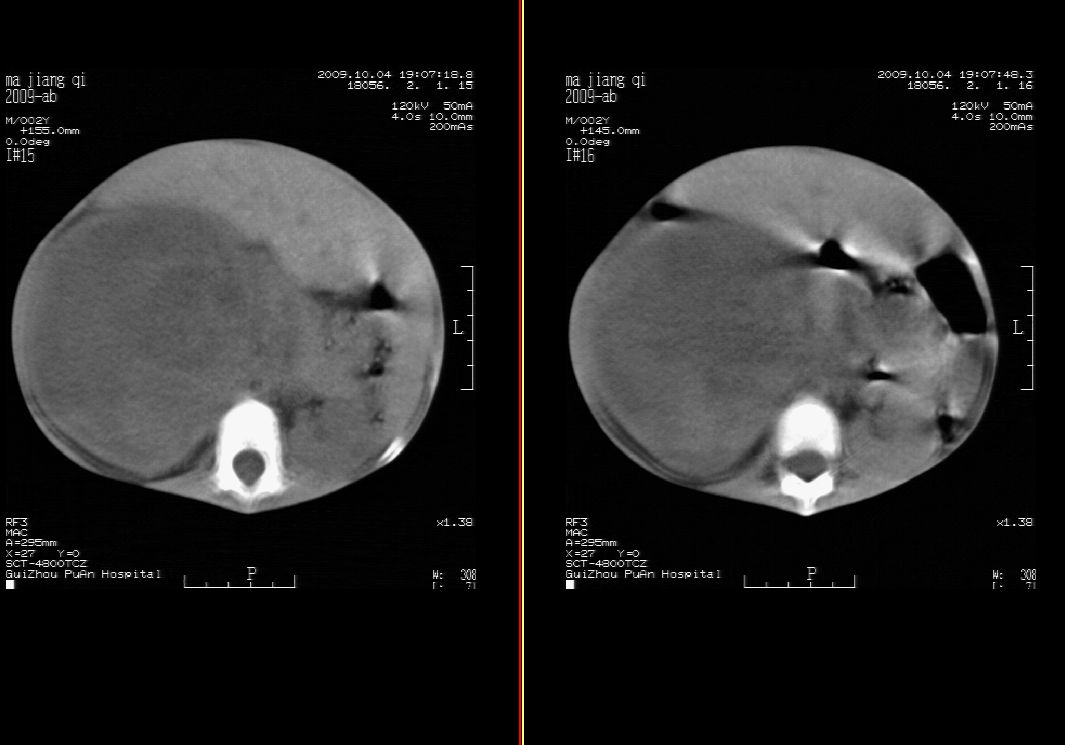

标题: PED2927:马某,男,两岁,发现血尿4天,请大家看看,发表 [打印本页]

标题: PED2927:马某,男,两岁,发现血尿4天,请大家看看,发表

右肾巨大囊性占位病变,其内密度不均,正常肾结构消失,肝脏,肾上腺及肠管等受压移位。双肺内多发大小不等的结节及块状影。考虑右肾母细胞瘤伴双肺多发转移。

肾母细胞瘤(wilms),系儿童最常见的恶性肿瘤,好发于3岁以下儿童,瘤体较大,主要由胚胎性肉瘤样细胞和上皮样细胞构成,临床以腹部肿块;血尿和高血压为主要体征。

ct表现:密度不均匀的大肿块存在;出血和坏死。与神母鉴别点:wilms易向颅脑转移,而神母易往肺转移。

ct表现:密度不均匀的大肿块存在;出血和坏死。与神母鉴别点:wilms易向肺转移。而神母易往颅脑转移.